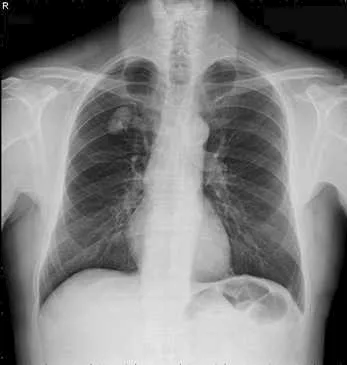

في أروقة مختبرات المستشفيات وعدسات الأطباء داخل أقسام الطوارئ، ظهرت نتائج تحاليل طبية وصفت بـ"الخارجة عن المألوف"، بعضها وصل حد الصدمة لما يحمله من أرقام غير قابلة للتصديق، وهذه الحالات، رغم ندرتها، تبقى بمثابة لغز يستفز العقل ويزيد من شأن المتابعة الطبية الاحترافية.